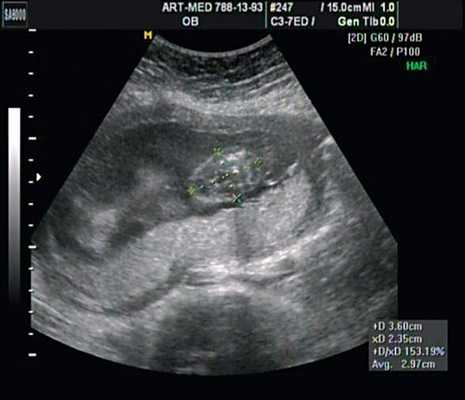

На рисунке - мультикистоз почки